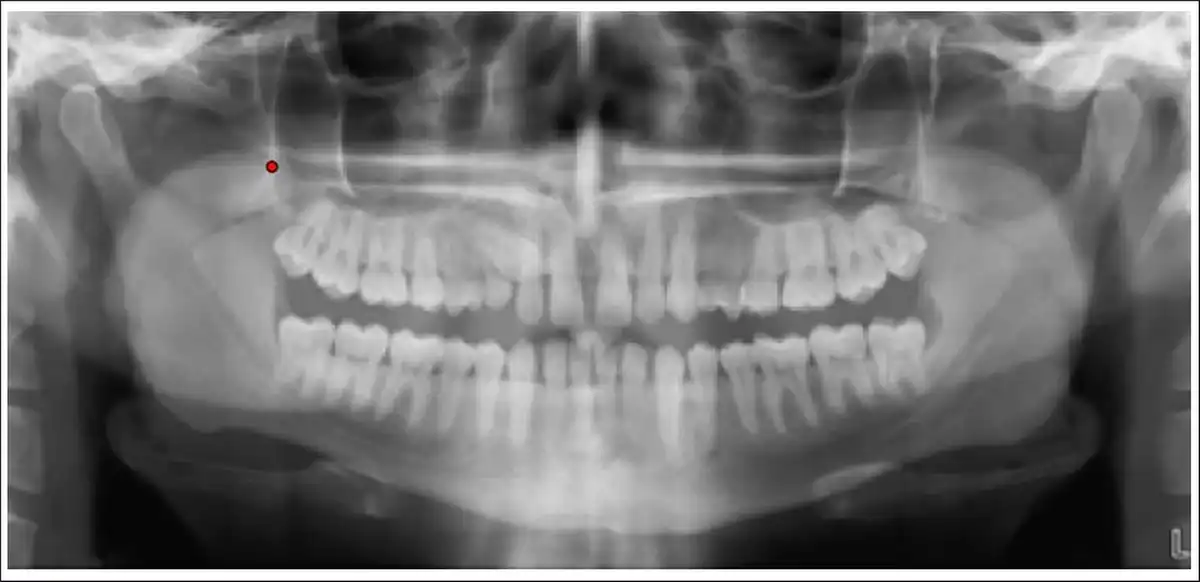

Step 1: The OPGs were uploaded in JPEG/TIFF format and cropped using a bounding box of uniform size of 80 × 215 pixels (Figures 2 and 3).

Point for Cropping Orthopantomogram.